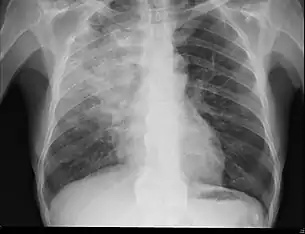

Radiography is the most common form of imaging used in the initial assessment of a foreign body presentation. Most patients receive a chest x-ray to determine the location of the foreign body.[2] Lateral neck, chest, and bilateral decubitus end-expiratory chest x-rays should be obtained in patients suspected of having aspirated a foreign body.[6] However, the presence of normal findings on chest radiography should not rule out foreign body aspiration as not all objects can be visualized.[2] In fact, up to 50% of cases can have normal findings on radiography.[7] This is because visibility of an object depends on many factors, such as the object's material, size, anatomic location and surrounding structures, as well as the patient's body habitus.[13] X-ray beams only show an object if that object's composition blocks the rays from traveling through, making it radiopaque and appearing lighter or white on the image. This also requires it to not be stuck behind something that blocks the beams first.[13] Objects that are radiopaque include items made of most metals except aluminum, bones except most fish bones, and glass. If the material does not block the x-ray beams it is considered radiolucent and will appear dark which prevents visualization.[13] This includes material such as most plastics, most fish bones, wood, and most aluminum objects.[13]

Signs on x-ray that are more commonly seen than the object itself and can be indicative of foreign body aspiration include visualization of the foreign body or hyperinflation of the affected lung.[13] Other x-ray findings that can be seen with foreign body aspiration include obstructive emphysema, atelectasis, and consolidation.[8]